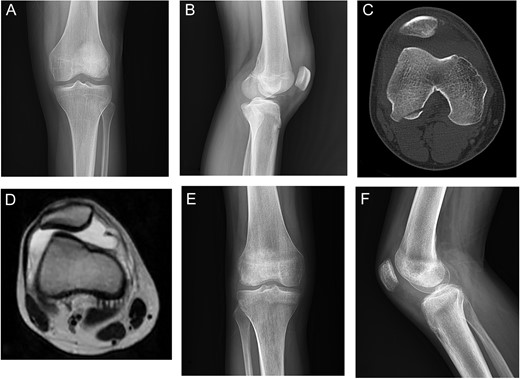

A 16-year-old male came with right knee pain and swelling after a twisting injury of the right knee while trying to break a wooden object with his left foot. Radiography showed a large OCF at the weight-bearing portion of the lateral femoral condyle [Fig.2A and B]. CT scan showed the bony avulsion from the medial facet of patella and the lateral femoral condyle OCF [Fig. 2C]. MRI showed lateral subluxation of patella [Fig. 2D]. Radiography, three months after the operation, showed complete union and the knee ROM was full [Fig. 2E and F].

Case 2. A and B Radiography showing lateral femoral condyle OCF and marked effusion. C, CT scan showing lateral patellar subluxation with medial patellar avulsion fracture and lateral femoral condyle OCF. D, MRI showing lateral patellar subluxation and marked joint effusion. E and F, 3 months postoperative radiography showing complete union.